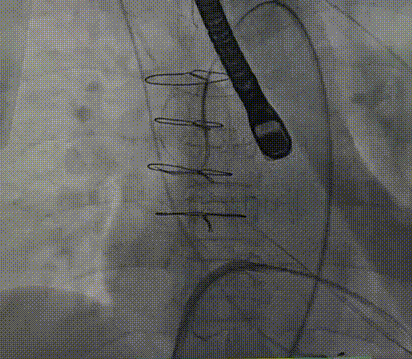

调整功率后行LAMPOON瓣叶切割术;

LAMPOON瓣叶切割

接着行经导管二尖瓣瓣中瓣置换术;

瓣膜定位后快速起搏下26mm SAPIEN 3稳定释放;

术前术后造影图对比